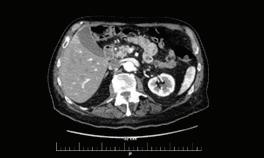

Д-р Екатерина Куртева

66 БЪБРЕЧНО-КАМЕННА БОЛЕСТЕТИОЛОГИЯ, ЧЕСТОТА, ЛЕЧЕНИЕ И ПРОФИЛАКТИКА В. Василев, Н. Димитров